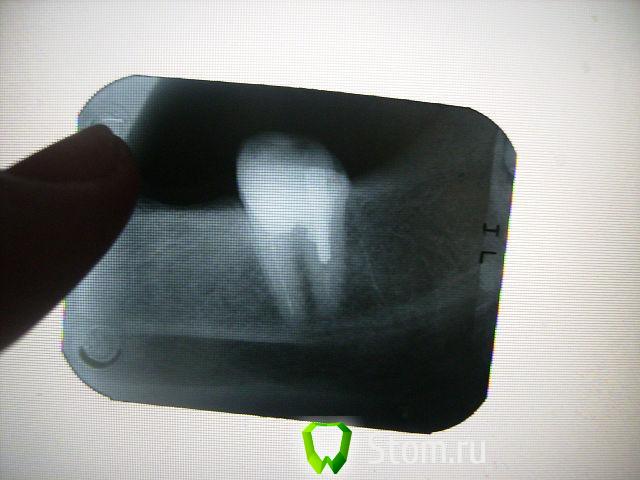

болящая Опубликовано 3 января, 2012 Поделиться Опубликовано 3 января, 2012 Уважаемые доктора! Перелечивала леченый 10 лет назад резорцин-формалиновый зуб (37).После перелечивания все дни боль при накусывании и ноющая самопроизвольная (10 дней) .Через 10 дней от перелечивания-свищ со щечной стороны с гнойным отделяемым ,боль ушла.Все дни обращалась к лечащему врачу. Ответ - все хорошо, на снимке каналы запломбированы отлично,а свищ-это реакция на перелечивание.То же сказал ортопед и закрепил мост на временный цемент (мост МК).Так ли хорошо на снимке с каналами,через неделю ставить мост на постоянный цемент, МК вещь не дешевая, что бы ее потом ломать. В настоящее время свищ закрылся, зуб не болит. Заранее спасибо за ответы. Ссылка на комментарий

DokDent Опубликовано 3 января, 2012 Поделиться Опубликовано 3 января, 2012 Уважаемые доктора! Перелечивала леченый 10 лет назад резорцин-формалиновый зуб (37).После перелечивания все дни боль при накусывании и ноющая самопроизвольная (10 дней) .Через 10 дней от перелечивания-свищ со щечной стороны с гнойным отделяемым ,боль ушла.Все дни обращалась к лечащему врачу. Ответ - все хорошо, на снимке каналы запломбированы отлично,а свищ-это реакция на перелечивание.То же сказал ортопед и закрепил мост на временный цемент (мост МК).Так ли хорошо на снимке с каналами,через неделю ставить мост на постоянный цемент, МК вещь не дешевая, что бы ее потом ломать. В настоящее время свищ закрылся, зуб не болит. Заранее спасибо за ответы. Я ничего хорошего не вижу.Свищ может открыться снова при обострении процесса. Ссылка на комментарий

DokDent Опубликовано 3 января, 2012 Поделиться Опубликовано 3 января, 2012 Спасибо за быстрый ответ! А можно поконкретней-что не так? Предположения любознательного рентгенолога,что есть еще один канал,который не пройден ни10 лет назад,ни сейчас.Неоднократные ответы доктора-все отлично,ничего болеть не может.Больше всего вводит в сомнение фраза-формирование свища при перелечивании каналов- благоприятный исход,свищ закроется и все будет хорошо! Каналы должны быть хорошо расширены,промыты и запломбированы на всём протяжении.На Ваших снимках этого нет.Если они плохо расширены,следовательно недомыты и незапломбированы как надо.Обострение периодонтита при перелечивании возможно,но если лечение проведено правильно-всё проходит,а если нет-может периодически повторяться. Ссылка на комментарий

болящая Опубликовано 4 января, 2012 Автор Поделиться Опубликовано 4 января, 2012 Зуб после первого посещения выглядел так(убрали старую пломбу,прошликанал 1-й и частично 2-й),временная пломба.Качество снимка отвратное.но другого нет. Ссылка на комментарий